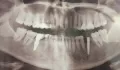

Имплант был установлен 3 месяца назад, когда установили формирователь десны, стало видно, что конструкция находится не посередине десны.

Конечно, Вы верно заметили, имплант стоит не посередине альвеолярного гребня. Возможно, хирург ставил имплант в область максимального объема кости, чтобы избежать дополнительной подсадки кости. Это вынужденная мера и довольно частое явление - хирург вкручивает имплант, куда ему удобно и где больше шансов на приживление, а протезист затем разбирается со смещенным положением.

Могу Вас успокоить вот чем - самое главное, чтобы на рентген-снимке врач увидел хорошее приживление импланта, а судя по Вашей фотографии, коронку изготовить возможно, хотя и немного сложно, но стоять она должна нормально.